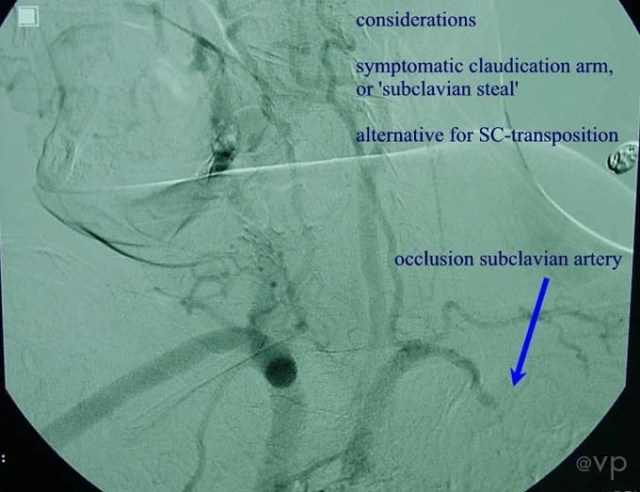

Carotid-Subclavian

| Carotid subclavian